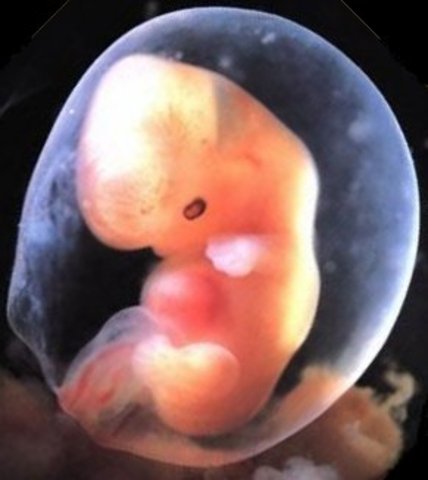

• week 4

week 4

This week marks the beginning of the embryonic period. From now until 10 weeks, all of your baby's organs will begin to develop and some will even begin to function. As a result, this is the time when she'll be most vulnerable to anything that might interfere with her development.